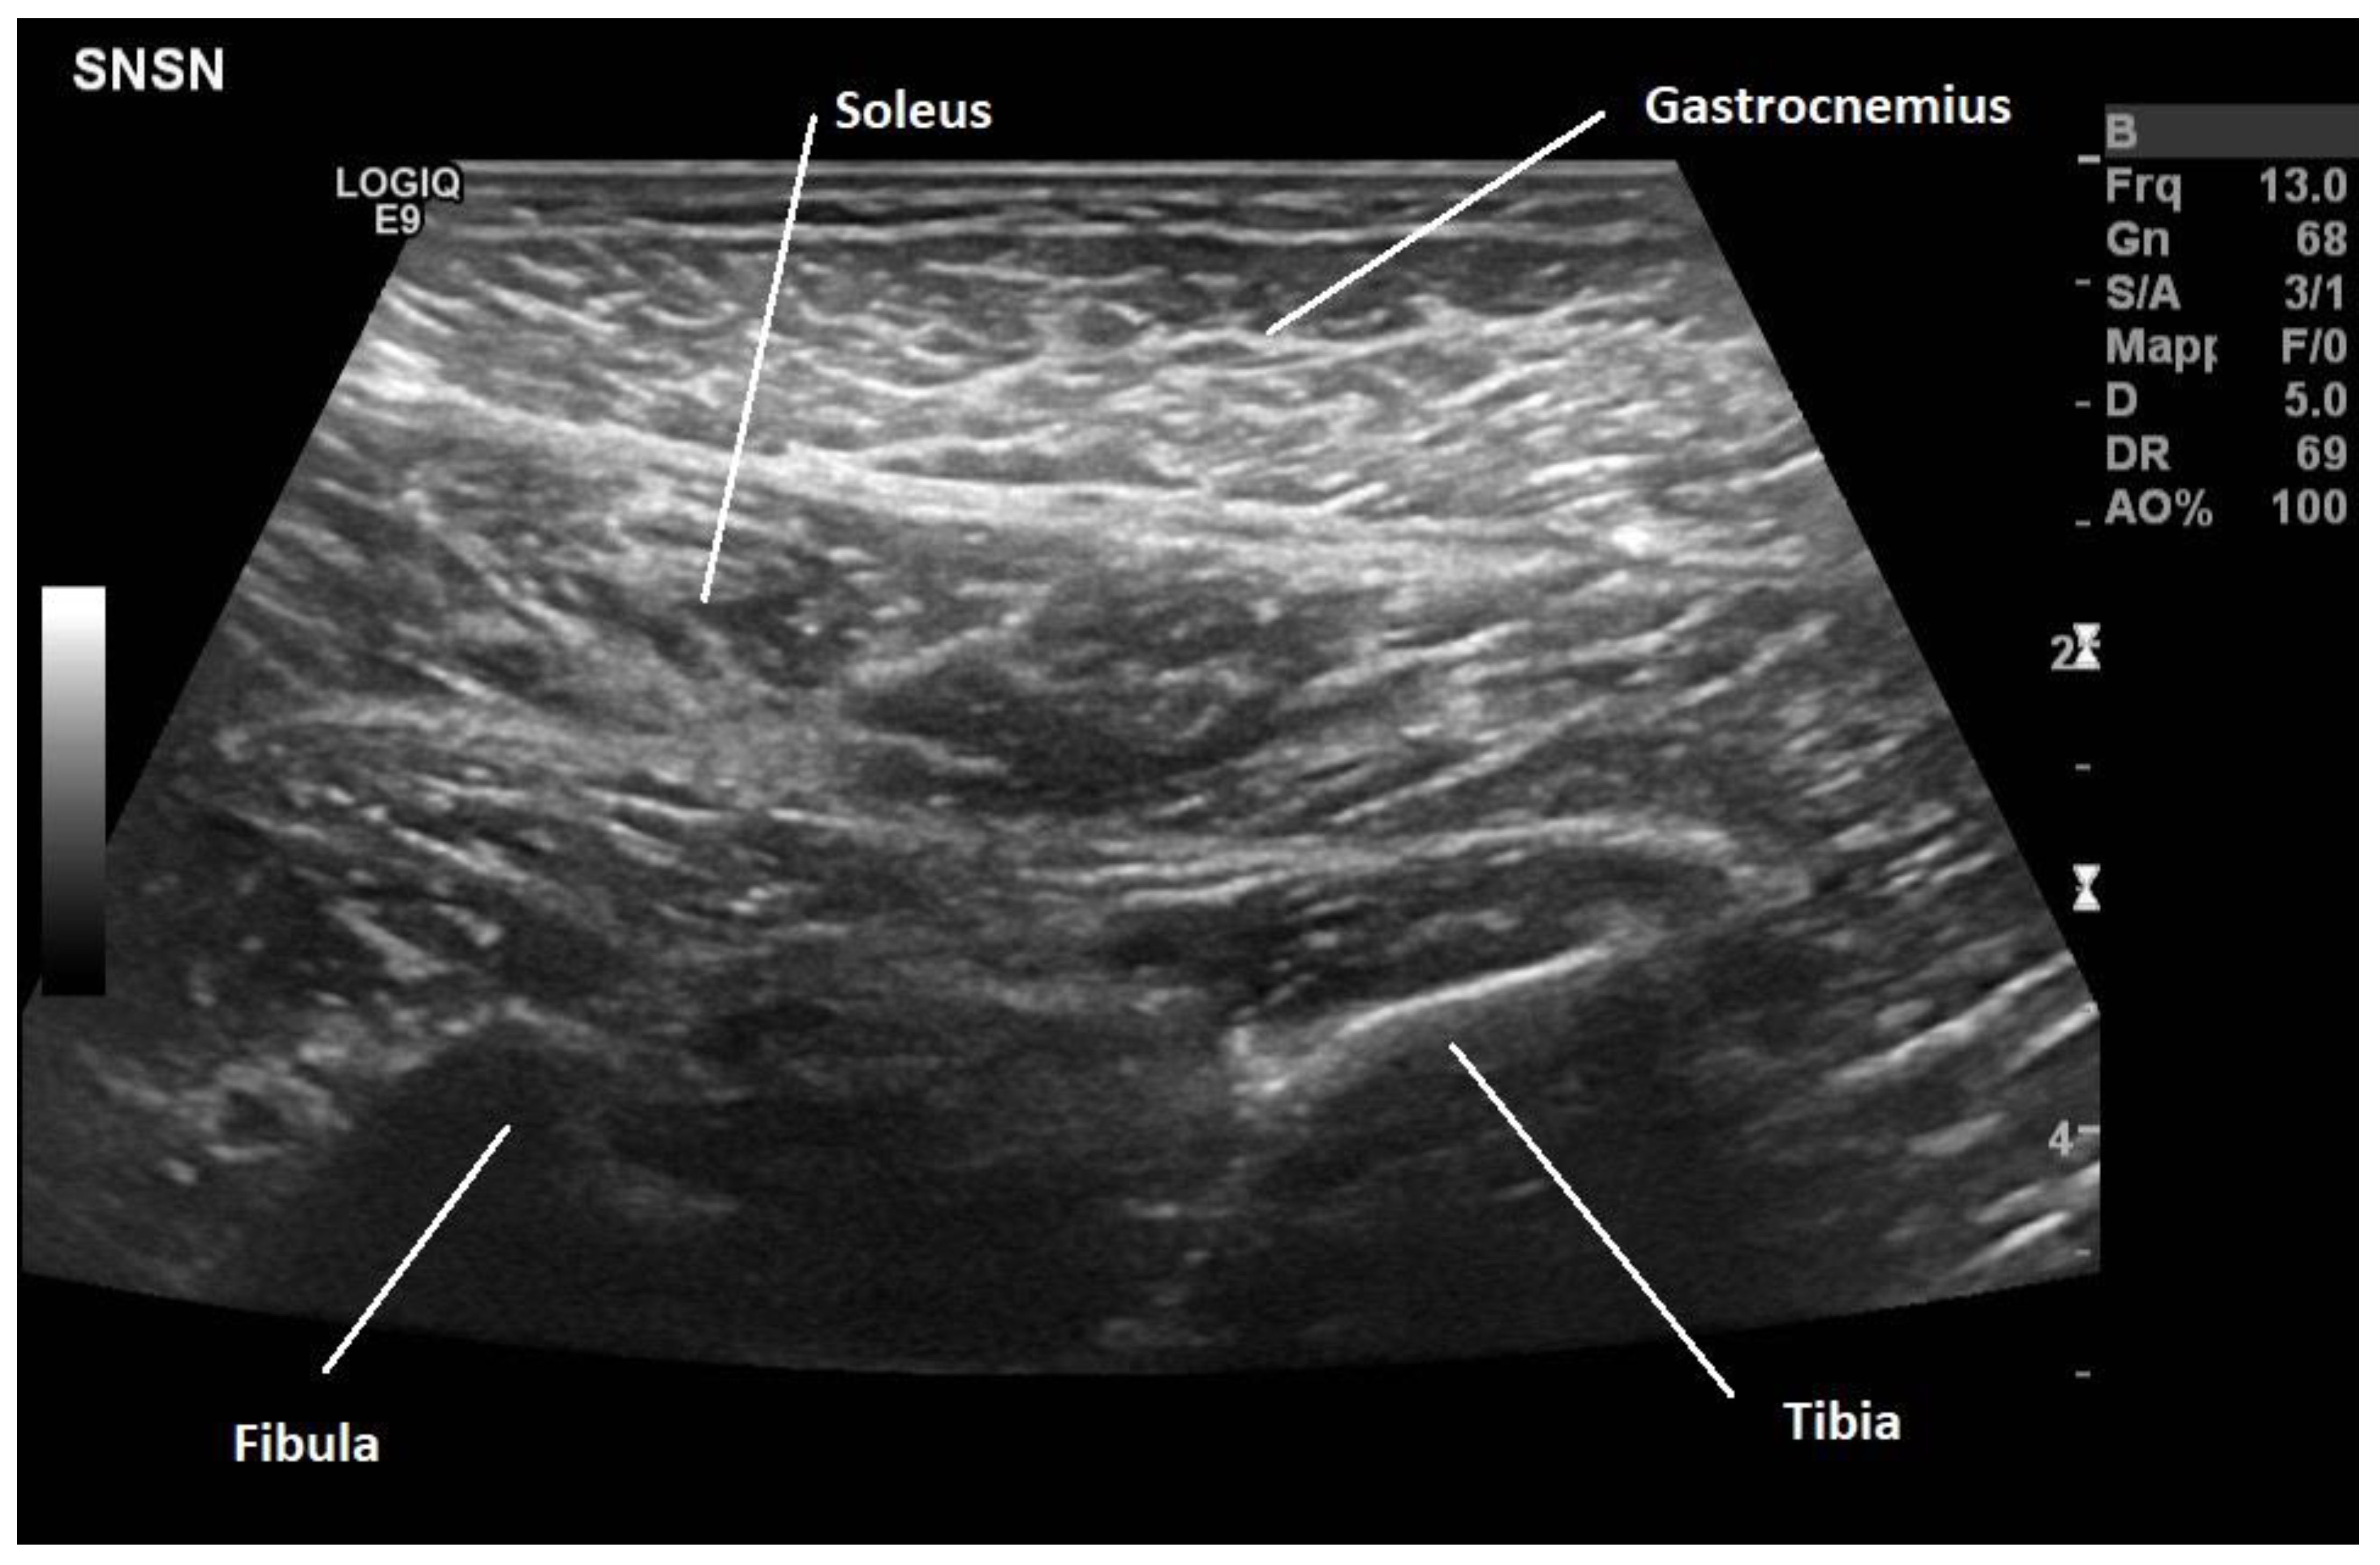

- Fietzek, U.M.; Nene, D.; Schramm, A.; Appel-Cresswell, S.; Košutzká, Z.; Walter, U.; Wissel, J.; Berweck, S.; Chouinard, S.; Bäumer, T. The Role of Ultrasound for the Personalized Botulinum Toxin Treatment of Cervical Dystonia. Toxins 2021, 13, 365. [Google Scholar] [CrossRef]

- Kaymak, B.; Kara, M.; On, A.Y.; Özçakar, L. A Novel Approach for Ultrasound-Guided Botulinum Toxin Injections: Botulis-MUS Projects. Am. J. Phys. Med. Rehabil. 2017, 96, e31. [Google Scholar] [CrossRef]